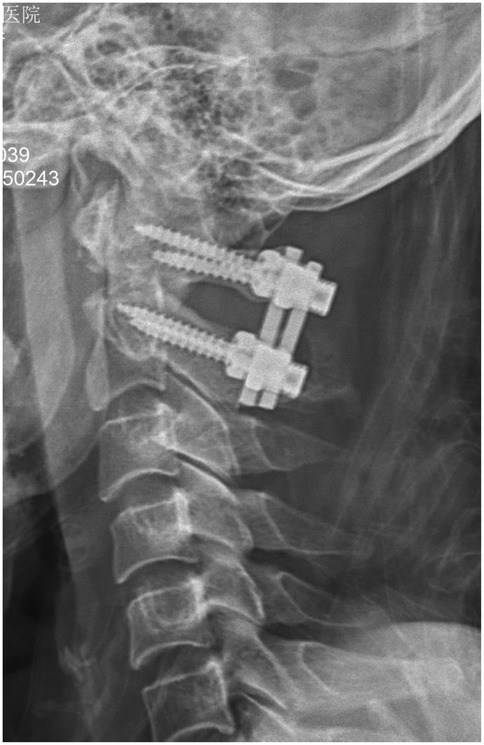

Objective: This retrospective study aimed to analyze the accuracy and safety of pedicle screw placement in upper cervical spine surgery for Hangman's fractures, particularly in cases with high-riding vertebral artery (HRVA) at C2, using navigation technology and 3D-printed patient-specific templates. Methods: We included 33 patients with Hangman's fractures who underwent posterior cervical fixation with bone graft fusion or non-bone graft fusion surgery between January 2013 and January 2023. Patients were divided into two groups based on the intraoperative pedicle screw placement method: Group A (n=15) utilized a navigation system, and Group B (n=18) used a 3D printed navigation template. Clinical and radiological data were collected and compared. Results: One hundred and forty-four screws (66 navigated, 78 3D-printed templates) were inserted without vertebral artery, spinal cord, or nerve injury. Operative time per screw: Group A 24.0±5.6 min vs Group B 18.7±4.1 min; mean difference 5.3 min (22% reduction; 95% CI -9.1 to -1.5; P=0.018). Intra-operative blood loss:152±29 mL vs 105±19 mL; mean difference 47 mL (95% CI -66 to -19; P=0.001). Overall accuracy (Grade 0+1) was 98.5% (65/66) vs 98.7% (77/78) (odds ratio 1.05; 95% CI 0.11-10.2; P=0.97). In the Type-III fracture subgroup (8 screws per group), templates achieved 100% accuracy vs 87.5% with navigation (P=0.032) and lower cortical penetration (12.5% vs 37.5%; P=0.008). Post-operative VAS and NDI improved comparably (all inter-group P>0.05). At 24-month follow-up, all fractures had healed; C2/3 fusion rates did not differ (facet fusion 100% vs 100%; inter-body fusion 39% vs 39%; P>0.99). Conclusion: The use of 3D-printed patient-specific templates in upper cervical spine surgery for Hangman's fractures, especially in the presence of HRVA, is effective and safe. It offers comparable accuracy to navigation-assisted surgery while reducing operative time and blood loss. This approach may be particularly beneficial in minimizing the risk of vertebral artery injury and optimizing surgical outcomes. Compared to navigation technology, it can effectively improve the accuracy of screw placement in extremely unstable fractures.